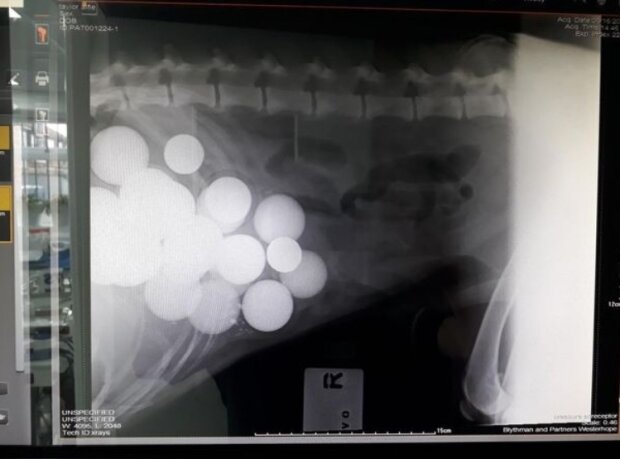

Golfové míče se pro Alfie ukázaly jako cukrová kost, a tak se během procházky mu podařilo sníst  jich až 26 kusů!

Pes samozřejmě potřeboval operaci! Chirurgové dokázali vytáhnout absolutně všechny koule.

Golfové míčky váží pouze 46 gramů, ale vzhledem k jejich počtu Alfie nesl v sobě více než kilogram tohoto vybavení!